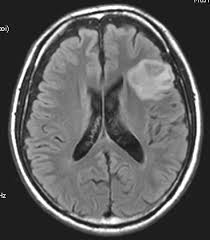

It never crossed my mind it could be something more sinister, was thinking maybe hemorrhage from the drunken antics or epilepsy.........did not think the lovely little English Dr would come in and say they had found a substantial "lesion" on my brain......what the heck is a bloody brain lesion?! So in that moment our lives changed.......

Then they sent off my scans to the "neuro gods" at RBH where they looked at them.......and it was then they decided it was a low grade benign tumour, with it's clear lines blah blah blah, we know how that story ended!! But this was the beginning.......

I was then shifted in to RBH, another ambulance ride!! Where I went through MORE MRI's and tests, and told AGAIN and AGAIN how it was a low grade benign tumour and should be fine after surgery........